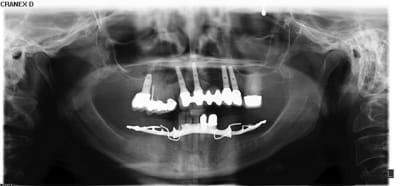

Bon la suite

Exo de 13-14-15 et greffe Bond-bone (mon 1er avec ce truc)

et Mineros (50-50)

--

et pour la suite, c'est 2 implants et bridge 13/15? (difficile d'avoir des certitudes quand au nombre d'implants...sans avoir tous les éléments...)

le bond bone, çà marche bien?